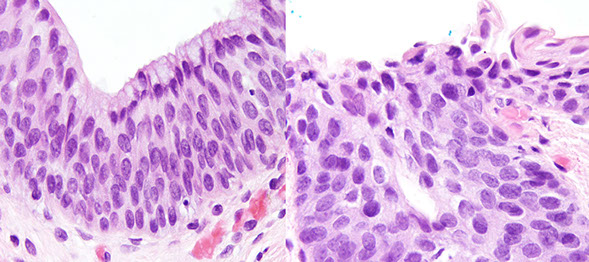

• Adenomas

• Tubular adenoma

• Tubulovillous and tubular adenomas

• Hyperplastic polyps

• Sessile Serrated polyp

• Serrated polyp / adenoma

Familial Adenomatous Polyposis (FAP)

• Colorectal adenocarcinoma

Colitis-associated Dysplasia and Colon Carcinoma

Dysplastic by definition, can be difficult to distinguish dysplasia from inflam; MC neoplastic polyps

- see lots of em in FAP

- initiation pt of adenoma is near mucosal surface, and grow in top-down manner, spreading into the crypts

Micro: elongated "pencil" hyperchromatic nuclei

- can see apoptotic bodies or clear-cell change, or squamous morules (similar to those in endometrium)

- larger villi can undergo crypt separation that may be reminiscent of a TV adenoma, but TV adenomas have long, well-formed finger-like villi

- can undergo striking gland prolapse, with glands in the submucosa which can look worrisome for invasive ca (called "pseudoinvasion"), except this usually take muscularis mucosa with it and the glands are more rounded and assoc c hemosiderin

No well-est criteria for HG-dysplasia, though size and probability of HG dysplasia are directly correlated

- if adenoma harbors carcinoma and invades lamina propria (Tis), still is equivalent as HG-dysplasia and polypectomy is curative

Tubular adenoma

asdf

Px: pts c 3+ adenomas, HG dysplasia, adenoma >1 cm or villous features need more intense FU

Tubulovillous (TVA) and Tubular adenoma

Not sure when to differentiate the 2

- no real consensus on what "villous" features are

- can probably just lump the 2 together and dx TVA when villi are well-formed